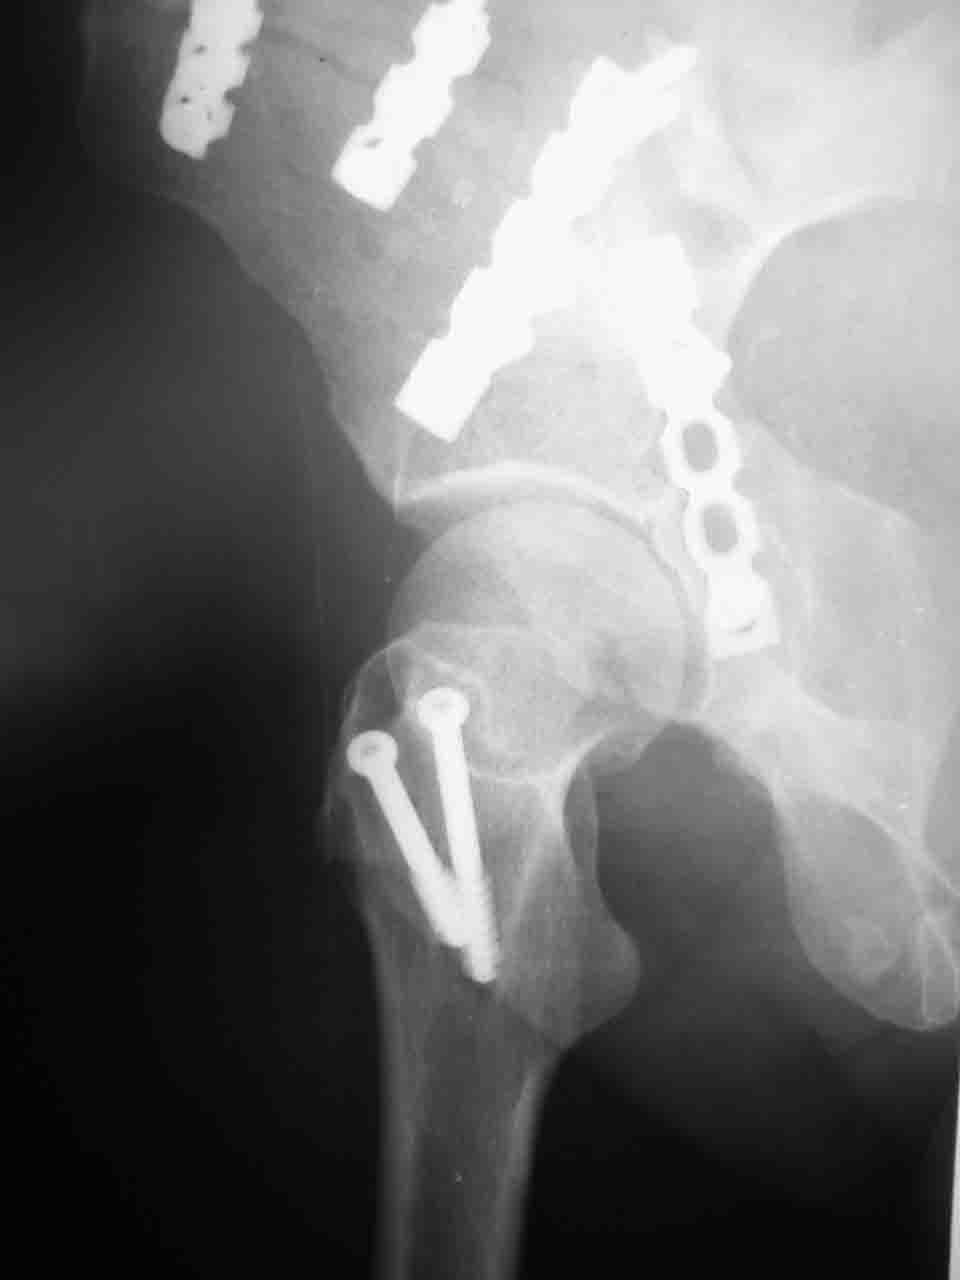

Сложностью, ассоциативностью характера перелома, я бы с радостью воспользовался мининвазивной перкутанной фиксацией винтами, но боюсь, что результат был бы ещё хуже, техникой непрямой репозиции перелома не владею, поэтому пытаясь получить анатомичную впадину приходится широко открывать, по крайней мере пока, а дальше буду пытаться уменьшать пространство...

> передним доступом на двухколонный перелом?

Илеофеморальный доступ не совсем передний и сравнительно с илеоингвинальным, и Кохера-Лангенбека открывает весь наружный таз кроме самых передних отделов лонных костей, фиксацию которых я не ставил в задачу. Обширность диссекции, большая длительность операции и более высокий риск гетерооссификации - отрицательные моменты в обмен на возможность легче ориентироваться.

Комбинированные доступы - хорошая альтернатива, меньший процент осложнений, но я заметил , что без сбора *мозаики* безымянной кости сложно отрепонировать переднюю колонну, а с нерепонированной передней колонной невозможно анатомично собрать заднюю колонну и соотв. фрагменты стенки - так.что все равно открывать придется широко. Поэтому выбирая комбинированный

подход, передний доступ должен был бы быть продлен до задней трети крыла безымянной кости, а задний - практически до того же уровня, оставляя 6-7 см мостик. При этом вместо одного послеоп. рубца у больного остаются два сравнительно длинных.

Вопрос доступа к вертлужной впадине при остеосинтезе задача не простая. Конечно, у Летурнеля и Тайла всё давно описано, нам остается только брать на вооружение. Но сами понимаете, что не бывает двух одинаковых ситуаций, поэтому в каждом случае вопрос решается сугубо индивидуально. Наша главная цель - восстановить анатомию с нанесением минимальной дополнительной травмы тазобедреннному суставу, думаю с этим никто не поспорит. Расширенный илиофеморальный доступ уж слишком травматичен (как сказал один коллега "таз лежит отдельно, больной отдельно").Стоит ли делать из пациента анатомический препарат для того чтобы легче ориентироваться. Да и нужно ли собирать всю "мозаику"? Мы применяли при таких операциях своеобразную операционную хитрость - сначала устраняли грубое смещение крыла под гребнем с фиксацией так называемой "плавающей" пластиной (временно фиксированной на двух винтах)- доступ или продлевали боковой, или делали небольшой дополнительный разрез над гребнем. Это позволяло устранить грубое смещение и захождение отломков тела повздошной кости, что значительно облегчало репозицию и остеосинтез впадины над сводом. Основное внимание конечно же уделяли нагружаемому задне-верхнему отделу. Сообщите ваш адрес, пришлю схемы и рентгенограммы.